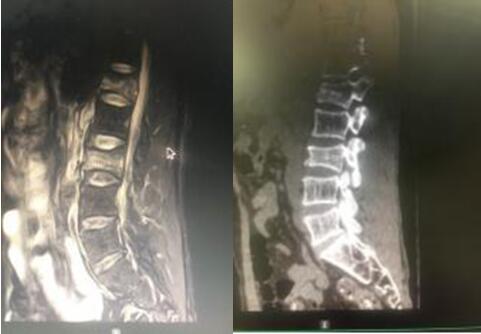

7月9日,經(jīng)與患者及其家屬充分溝通后,在脊柱外科蘇光輝主任、汪向東副主任帶領下順利進行了經(jīng)皮跨傷椎長節(jié)段后路內固定手術治療腰椎骨折。術后傷口小、出血量極小約50ml,術后1周即可下地行走,患者及其家屬對手術效果相當滿意。

術后